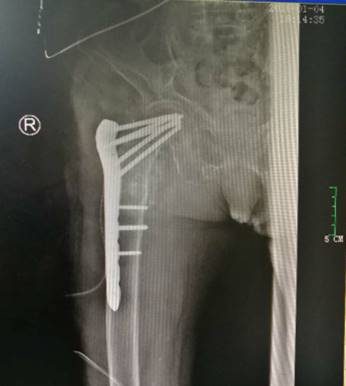

经过术前的充分准备,在老太太入院后第二天即行手术治疗。吕浩然主任带领的骨科团队在麻醉科、手术室、输血科、心血管内科及ICU医护人员全力配合下开展手术。吕主任凭着娴熟的手术技巧和丰富经验,对右侧股骨粗隆间骨折处解剖复位并固定,每个动作均准确到位。整个手术团队密切配合,牵引、复位、内固定等一气呵成。当老太太平安送出手术室门口时,久久等待的家人眼含热泪,感激之情溢于言表。术后,团队应用先进的“ERAS术后快速康复理念”帮助患者较好地恢复。目前老太太伤口愈合良好。

ERAS术后快速康复